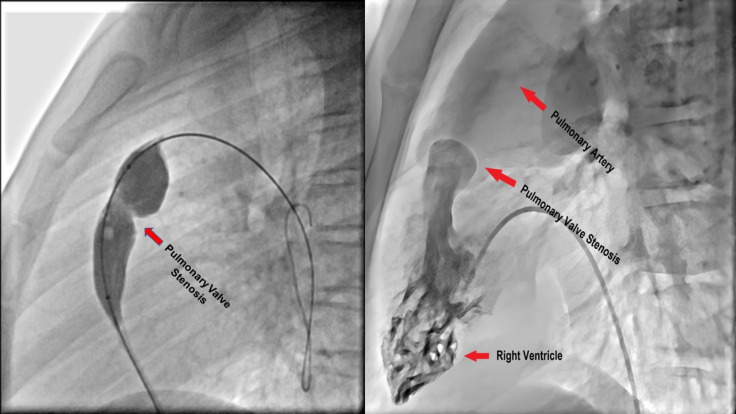

Background: Balloon Pulmonary Valvuloplasty (BPV) is a procedure for Pulmonary Stenosis (PS) treatment. In this study, right ventricle (RV) performance was determined through 2D-Speckle Tracking Echocardiography (2D-STE).

Methods: The study involved 25 diagnosed children with PS undergoing BPV and 25 normal children. They were examined using 2D-STE and Linear Mixed Model (LMM) approach was used to determine changes in Pulmonary Valve Peak Gradient (PVPG), Tricuspid Annular Plane Systolic Excursion (TAPSE), strain and Strain Rate (SR) for RV, and Ejection Fraction for Left Ventricle (LVEF).

背景:球囊肺动脉瓣成形术(BPV)是治疗肺动脉狭窄(PS)的一种方法。本研究通过二维斑点追踪超声心动图(2D-STE)确定右心室(RV)的性能:研究涉及 25 名确诊为 PS 并接受 BPV 治疗的儿童和 25 名正常儿童。研究使用二维啄木鸟跟踪超声心动图(2D-STE)和线性混合模型(LMM)方法对他们进行检查,以确定肺动脉瓣峰值阶差(PVPG)、三尖瓣环平面收缩期偏移(TAPSE)、左心室应变和应变率(SR)以及左心室射血分数(LVEF)的变化:两组在 TAPSE(P=0.001)、整体应变(P=0.001)、室间隔顶端应变(P=0.024)、室间隔中部应变(P=0.001)、室间隔基底应变(P=0.001)、室间隔顶端侧 SR(P=0.001)、室间隔中部侧 SR(P=0.007)、室间隔基底侧 SR(P=0.001)和室间隔顶端 SR(P=0.001)方面存在显著差异。BPV 后,LVEF(P=0.001)和 TAPSE(P=0.001)增加,但 PVPG 下降(P=0.001)。BPV 后,观察到心尖外侧应变(P=0.004)、室间隔中部应变(P=0.001)、心尖室间隔应变(P=0.003)、室间隔中部应变(P=0.001)、室间隔基底应变(P=0.048)、心尖室间隔 SR(P=0.025)和室间隔中部 SR(P=0.023)增加。性别与基底侧应变(P=0.019)、中隔应变(P=0.037)和中隔SR(P=0.020)的平均变化显著相关。PS患儿的年龄与基底室间隔应变(P=0.031)和基底室间隔SR(P=0.018)的平均变化有关:结论:PS患儿室间隔应变和SR在BPV术后有所改善。儿童的性别和年龄对 BPV 后 RV 应变和 SR 变化有显著影响。